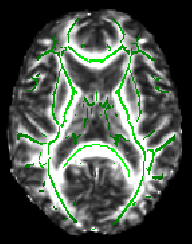

The -dr option sets sensible display range options, and in the case of the skeleton image, also controls the thresholding applied. Now turn on the movie loop; you will see the mean FA skeleton on top of each different subject's aligned FA image. If all the processing so far has worked ok the skeleton should look like the examples shown here (see the TBSS paper for more examples of different subjects' results underneath the skeleton). If the registration has worked well you should see that in general each subject's major tracts are reasonably well aligned to the relevant parts of the skeleton. If you set the skeleton threshold (in FSLeyes, the lower of the display range settings) much lower than 0.2, it will extend away towards extremes where there is too much cross-subject variability and where the nonlinear registration has not been able to attain good alignments. Remember the skeleton threshold for the next stage.

All of the above (apart from setting the skeleton transparency, which has to be done by hand in the GUI) can be carried out with a single command (see first example image):

fsleyes $FSLDIR/data/standard/MNI152_T1_1mm mean_FA_skeleton -cm green -dr 0.2 0.7 tbss_tfce_corrp_tstat1 -cm red-yellow -dr 0.95 1